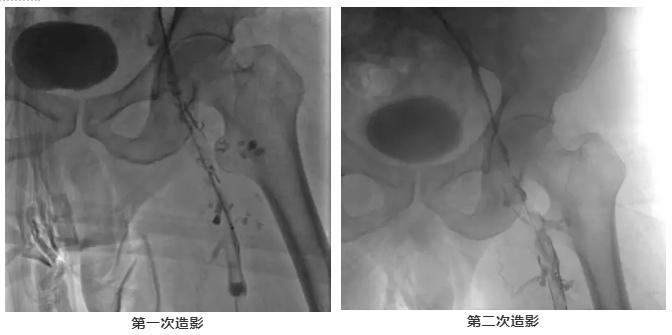

次日为进一步治疗在介入手术室行“选择性静脉造影术+经皮静脉内滤网置入术+经皮静脉插管药物灌注术”术后持续尿激酶、肝素抗凝治疗,维持APTT60-80s。

8月22日为进一步了解溶栓效果,行“经皮选择性静脉造影术+经皮静脉球囊扩张术”。